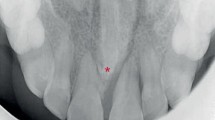

In the present study, we selected four Japanese families, Families A, B, C, and D. In three families (Families A, B and D), both first and second generations have supernumerary teeth. We do not know whether the first generation in Family C is affected. However, the second generation in Family C has impacted supernumerary teeth in the maxillary incisor area. Most affected individuals have one supernumerary tooth; however, II-2 in Family A has two (Figure 1a, b). The occurrence of supernumerary teeth in most of these families indicates an autosomal-dominant pattern of inheritance. All subjects were diagnosed by examining a panoramic radiograph or upper anterior occlusal radiographs and interviewing the patient about their medical and dental history. All subjects were free of any syndrome or congenital anomaly such as cleft lip or palate. All subjects provided written informed consent and the study was approved by the Ethics Committee of Showa and Kanazawa University.

(a) Upper anterior occlusal radiograph of II-2 in Family A with two impacted supernumerary teeth in the maxillary incisor area. (b) Family pedigrees of Japanese individuals with supernumerary teeth. Squares and circles denote males and females, respectively. Filled symbols indicate affected individuals. The phenotype of the first generation in Family C is unknown.